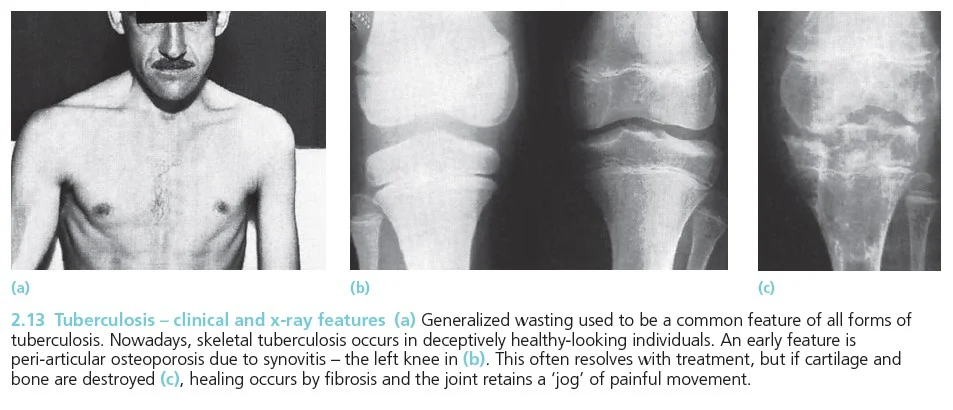

Plain X-rays

- Joints: usually monoarticular

- Peri-articular osteopenia

- Subchondral and peripheral erosions affecting both sides of the joint

- Loss of joint space